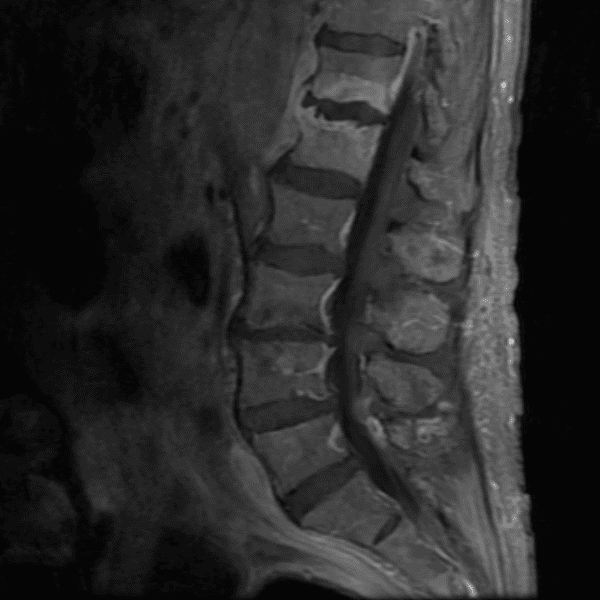

Simulates call by including subtle or difficult cases and some normals.

35 cases